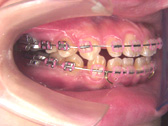

実際の治療  ( 実際に当クリニックで治療を終了された患者さんの写真を、許可を得て掲載しております。) 特別治療 【裏側矯正】 歯の裏側に矯正装置を装着して治していく治療法です。表側から装置が目立たないのが特徴です。

歯に矯正器具をつけ歯を動かして治療します。矯正器具は 金属のもの、セラミックの もの、裏側からつけるものがあります